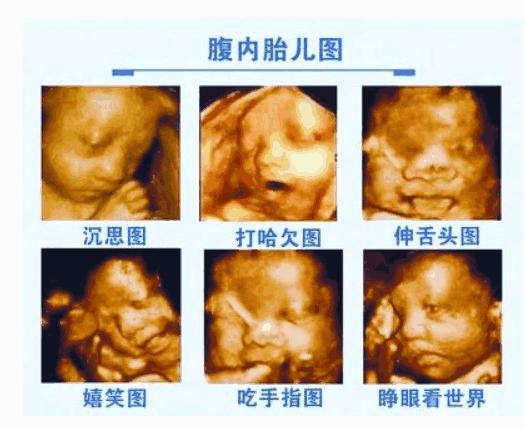

四维彩超是最先进的超声设备,可以更加清楚的看到胎宝宝的发育情况,还可以看到宝宝发育的是否有缺陷,做四维彩超的最佳时间是在孕期20周到28周之间,这个时间段的胎宝宝各个器官基本发育完成,是最适合跟宝宝见面的时候,但是很多时候当孕妈妈准备好了要跟宝宝见面的时候,宝宝却不配合了!宝宝睡着了,妈妈很受累!所以,需要提前跟宝宝做好准备,告诉他,我们要照相了,可不能睡觉哦!